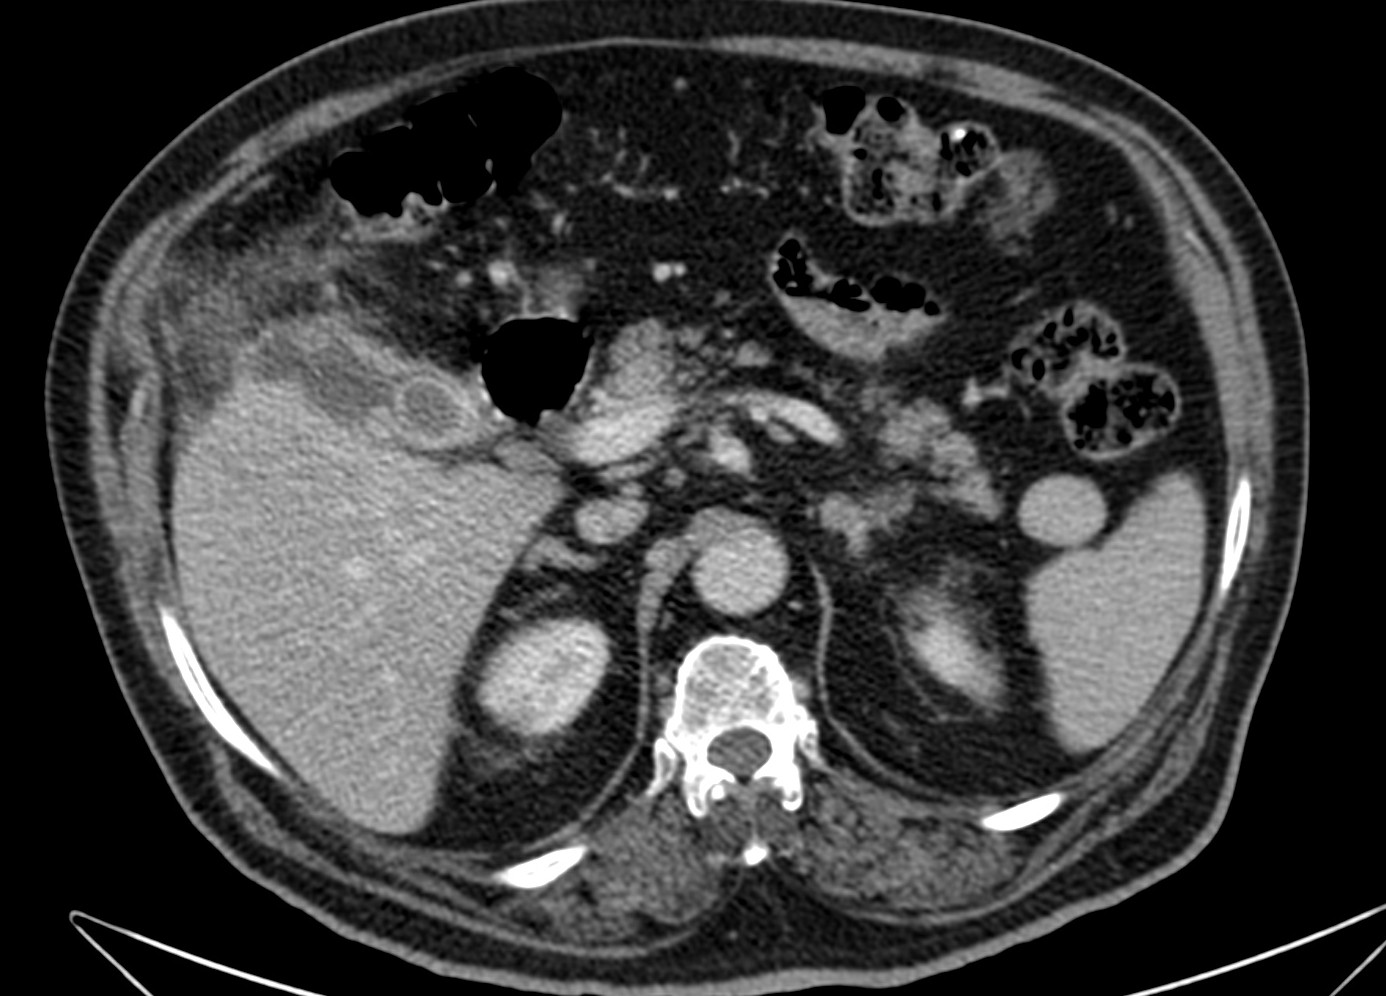

Se realizó posteriormente TC abdominal por mala evolución del paciente:

– La TC se reserva para pacientes con dudas diagnósticas o con discrepancia clínico ecográfica. Se obervarán los mismos hallazgos que en la ecografía, además del aumento de densidad de la pared de la vesícula, del parénquima hepático o especialmente la presencia de otras complicaciones.

- Colecistitis xantunogranulomatosa: nódulos o bandas intramurales. Se producen por la oclusión de los senos de Rokitansky Aschoff de la pared, los cuales se rompen, luego la bilis coloniza la pared y finalmente produce una reacción inflamatoria a la que puede sobreañadirse una infección. Es un factor de riesgo para el carcinoma.

- Eco y TC: Litiasis + engrosamiento mural focal o difuso. Puede haber cambios inflamatorios pericolecísiticos. Los nódulos hipocogénicos o bandas pueden sugerir el diagnóstico específico de c. xantunogranulomatosa.

- El diagnóstico raramente se realiza previo a la cirugía y al análisis histopatologíco.